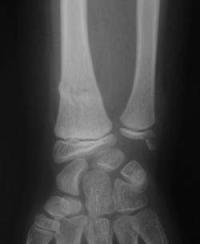

Fracture métaphysaire distale du radius : radio de Profil initiale

Noter la pliure postérieure source d'instabilité